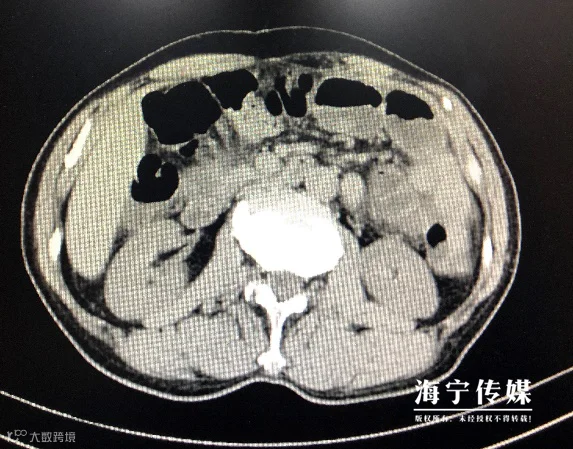

然而几天后,朱大夫最担心的事发生了。复查腹部CT提示胃里的石头跑去肠里,并发了“肠梗阻”。所幸的是,这回发现及时,经过几天治疗,石头还是下去了。